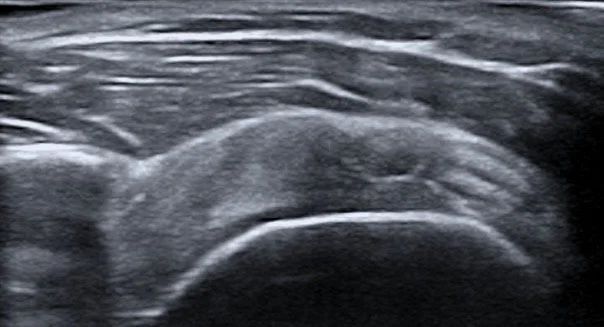

Imagen de una ecografía médica en tonos grises.

El PRP y la proloterapia se inyectan con mayor precisión bajo guía ecográfica en la articulación del hombro, así como en tendones y ligamentos. Se requiere amplia experiencia en el uso de ecografía para aplicar estos tratamientos de medicina regenerativa y así asegurar una mayor eficacia. Todas las inyecciones de PRP o Proloterapia se realizan bajo guía ecográfica logrando mayor precisión, colocando el tratamiento en el sitio correcto de la lesión que ocasiona su dolor. Se tratan todas las estructuras del hombro (articulaciones, ligamentos, tendones, músculos y nervios)